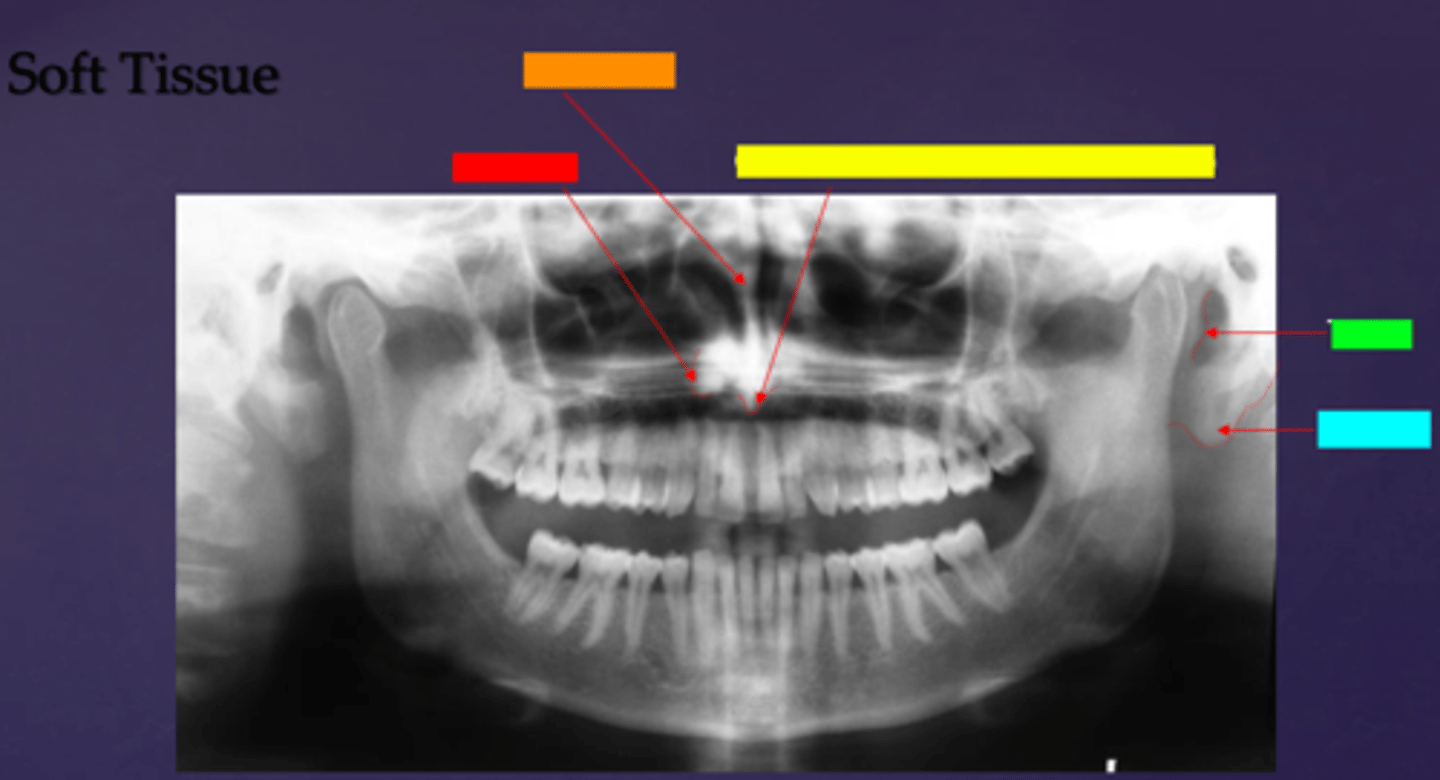

ID the soft tissue anatomy indicated by the arrow pointing from the red box:

posterior pharyngeal wall

ID the soft tissue anatomy indicated by the arrow pointing from the orange box:

soft palate

ID the soft tissue anatomy indicated by the arrow pointing from the yellow box:

dorsal surface of tongue

ID the soft tissue anatomy indicated by the arrow pointing from the green box:

middle nasal meatus

ID the soft tissue anatomy indicated by the arrow pointing from the light blue box:

inferior nasal meatus

ala of nose

nasal septum

columna (the septum separating the nostrils)

tragus

ear lobe